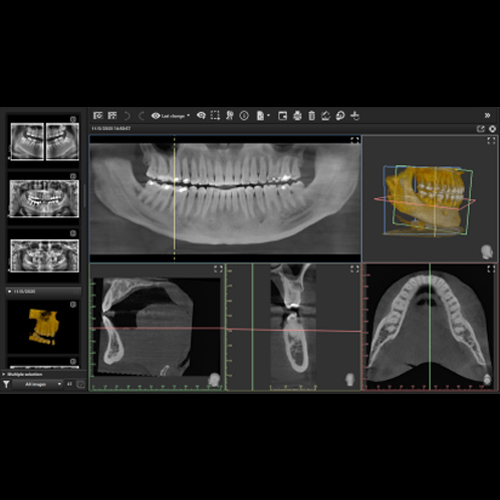

Leveraging AI for Diagnostic Excellence

The newest advancements in diagnostic imaging incorporate assisted intelligence (AI). Software can now help dentists more precisely and accurately identify areas of concern, trace the mandibular nerve, accurately plan dental implants, organize all images into a single template, and much more.

Maximizing Efficiency in Digital Imaging

To optimize a digital imaging armamentarium, there are several factors to consider. Important considerations include coordinating many different types of workflows, ensuring that all images are instantly accessible across all screens, the ability to securely store data in the cloud, and being able t...

Next-Level Clinical Precision With Advanced Imaging

Digital radiography is no longer the future of dental care, but an expected standard and a requirement to meet new regulations. Its integration into each practice, however, is a continual process to maximize the value of this investment. This eBook focuses on important advancements in various dental...

Interaction of CBCT, Intraoral Scanning, and CAD/CAM in Dentistry: An Overview

Friday, January 31, 2020

Digital Workflow and Prosthetically Driven Implant Placement

When it comes to successful implant placement, a design that begins with the end result in mind is important. A well-designed case not only assists in optimizing implant position but also allows clinicians to start contouring the emergence profile at implant placement. In this eBook, Dr. Bart Silver...